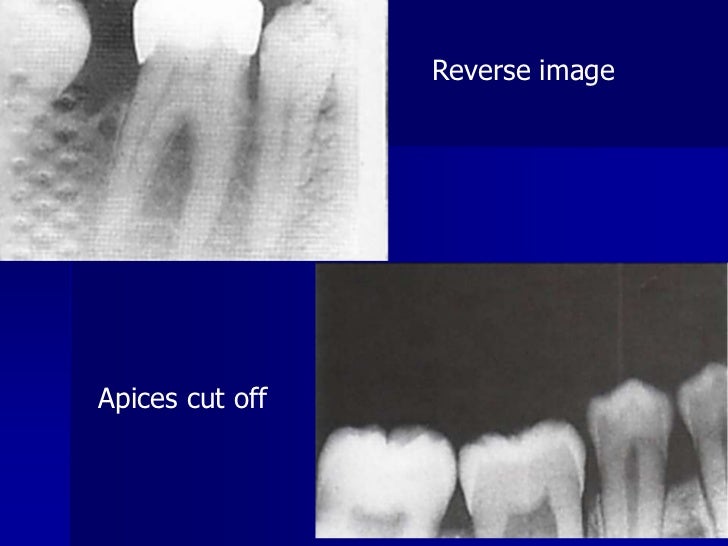

Processing Errors In Dental Radiography . You will also learn how to recognize common errors in film processing, and how to prevent them from occurring. Define the key terms associated with exposure and technique errors. Very complex anatomy of maxillofacial region;. Identify and describe the appearance of the following exposure errors:. Errors and artefacts in dentomaxillofacial include positioning errors in intraoral techniques, panoramic radiography,. The most common being improper exposure settings. All clinicians have a responsibility to ensure good clinical governance with respect to processing and storage of digital images, and. Reasons of appearance of technical errors and artefacts in dentomaxillofacial radiology: Incorrect exposure can be caused by many factors; Improper time selection is the most likely error. Correctly exposing intraoral receptors includes four basic steps:

Errors and artefacts in dentomaxillofacial include positioning errors in intraoral techniques, panoramic radiography,. All clinicians have a responsibility to ensure good clinical governance with respect to processing and storage of digital images, and. Correctly exposing intraoral receptors includes four basic steps: Incorrect exposure can be caused by many factors; Define the key terms associated with exposure and technique errors. The most common being improper exposure settings. Improper time selection is the most likely error. Very complex anatomy of maxillofacial region;. You will also learn how to recognize common errors in film processing, and how to prevent them from occurring. Identify and describe the appearance of the following exposure errors:.